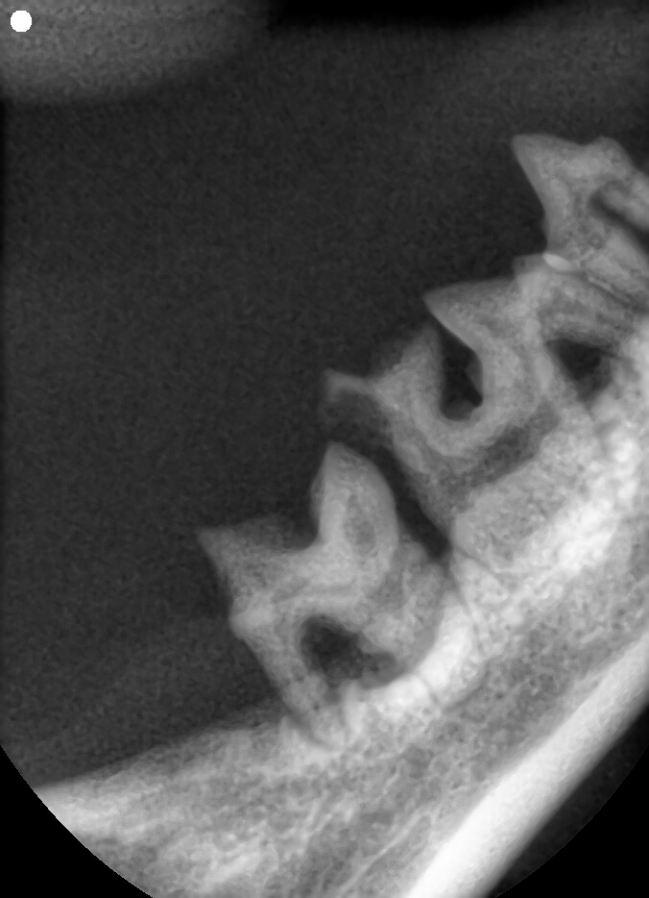

치료중 대상묘